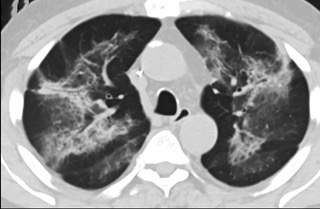

疑点一,电子烟患者的CT影像和临床表现并不具有特异性。所谓美国电子肺炎患者,其实是对没有其他合理诊断证据、吸食电子烟肺炎患者的统称。这些患者在病发前90天内吸食了电子烟,尤其值得注意的是,部分患者的CT影像特征和临床表现与病毒性肺炎患者极其相似。

疑点二,中国科研工作者从60篇研究论文中筛选出142位电子烟肺炎患者的250张影像图片,邀请3位放射科权威专家,对上述全部影像图片、相关病人临床信息以及文献原文进行了仔细全面研究与审查,又有了新的发现。

16位被文献报道为电子烟肺炎的患者被专家判定为“病毒性感染”,即有可能是新冠肺炎的“疑诊患者”,其中更有5位临床症状和治疗情况相对完整的患者被判定为“中度可疑”。因此在2019年美国报道的电子烟肺炎中存在病毒性感染的病例,而且不排除美国电子烟肺炎中存在新冠肺炎的可能性。